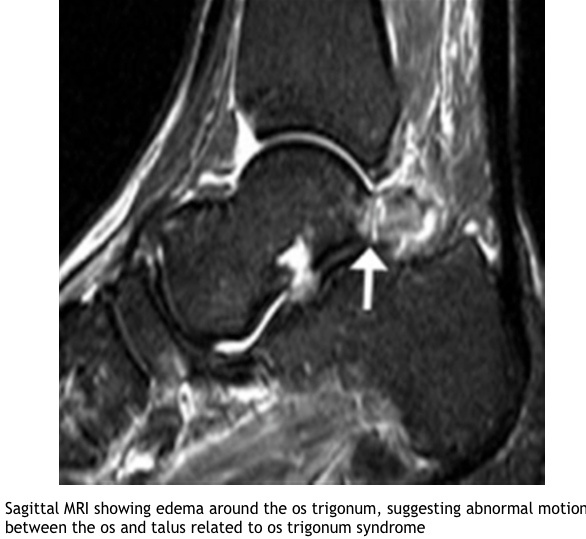

What investigations are useful in Os trigonium?

What is the Differential dx of Os trigonium ?